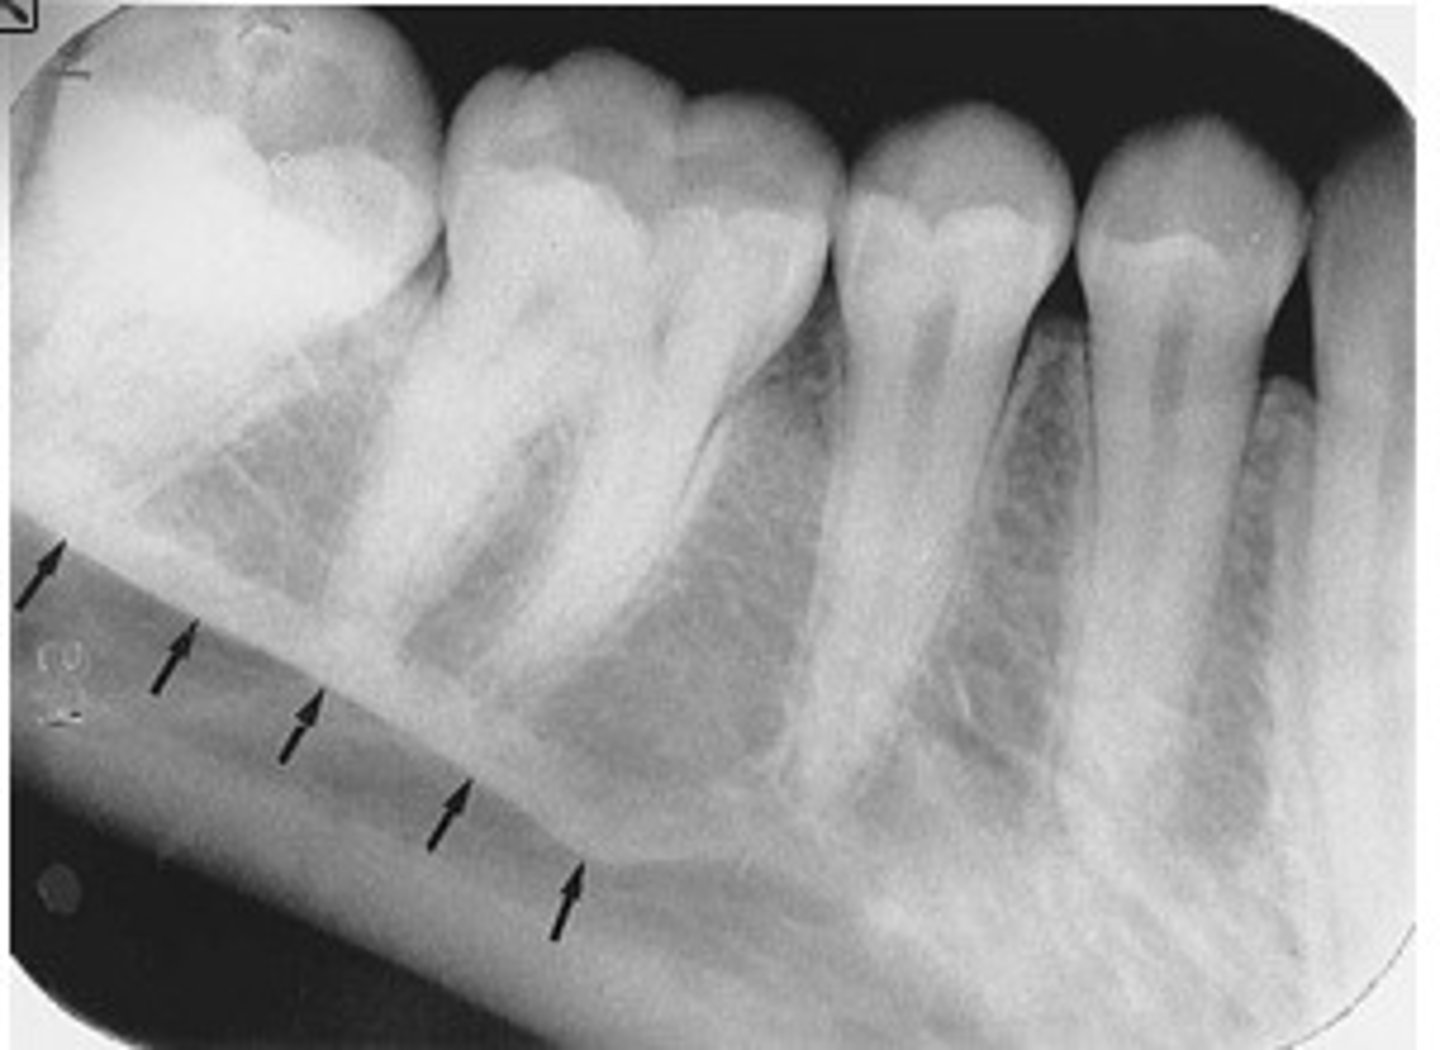

Mandibular canal

What is the radiolucent structure seen here?